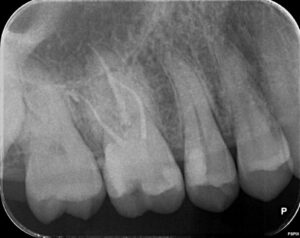

他院で治療をしてもらったが、痛みがずっと続く、ということで当院に来られました。診査の結果、右上6番目の歯の神経が細菌感染を起こしているため、痛みが続いているとわかりました。そこで、2回に分けて、根管治療と修復処置を行いました。

横の右上5番目の歯は神経近くまで虫歯は進んでいましたが、神経を保存することが出来ました。